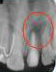

PRF Mediated REP in 21 with 18 Months Follow Up

Complete Bony Healing, Apex Closed, Lateral Wall Thickening- 15.5%

PRF Mediated REP in 21 with 26 Months Follow Up

Complete Bony Healing, Apex Closed, Lateral Dentinal Wall Thickened, PDL Apically